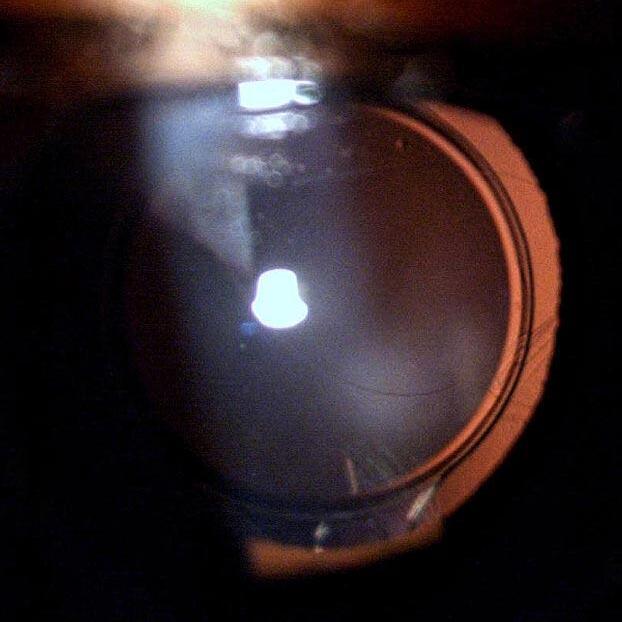

La rotura de cápsula posterior (RCP) es una de las complicaciones más frecuentes en la cirugía de facoemulsificación con reportes entre 0,5% y 5,2%. La prevalencia de la misma disminuye notablemente si se tienen los reparos necesarios para su preservación, principalmente en la técnica de facoemulsificación y los parámetros utilizados en el equipo. La estabilidad de la cámara anterior en los últimos fragmentos es clave para la seguridad siendo los principales factores el vacío máximo programado en el equipo con el consecuente surge tras la desoclusión de la punta (Imagen 1) , la pérdida incisional de líquido y la tecnología compensatoria que nos pueda ofrecer cada equipo.

Imagen 1.